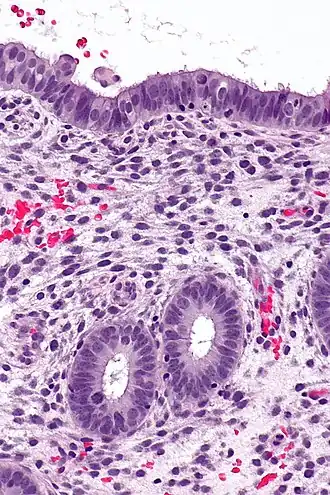

![]() Endometrium in the proliferative phase | |

Structure

The endometrium consists of a single layer of columnar epithelium plus the stroma on which it rests. The stroma is a layer of connective tissue that varies in thickness according to hormonal influences. In the uterus, simple tubular glands reach from the endometrial surface through to the base of the stroma, which also carries a rich blood supply provided by the spiral arteries. In women of reproductive age, two layers of endometrium can be distinguished. These two layers occur only in the endometrium lining the cavity of the uterus, and not in the lining of the fallopian tubes where a potentially life-threatening ectopic pregnancy may occur nearby.[4][5]

- The functional layer is adjacent to the uterine cavity. This layer is built up after the end of menstruation during the first part of the previous menstrual cycle. Proliferation is induced by estrogen (follicular phase of menstrual cycle), and later changes in this layer are engendered by progesterone from the corpus luteum (luteal phase). It is adapted to provide an optimum environment for the implantation and growth of the embryo. This layer is completely shed during menstruation.

- The basal layer, adjacent to the myometrium and below the functional layer, is not shed at any time during the menstrual cycle. It contains stem cells that regenerate the functional layer,[1] which develops on top of it.

It is possible to identify the phase of the menstrual cycle by reference to either the ovarian cycle or the uterine cycle by observing microscopic differences at each phase—for example in the ovarian cycle:

| Phase | Days | Thickness | Epithelium |

|---|---|---|---|

| Menstrual phase | 1–5 | Thin | Absent |

| Follicular phase | 5–14 | Intermediate | Columnar |

| Luteal phase | 15–27 | Thick | Columnar. Also visible are arcuate vessels of uterus |

| Ischemic phase | 27–28 | Columnar. Also visible are arcuate vessels of uterus |